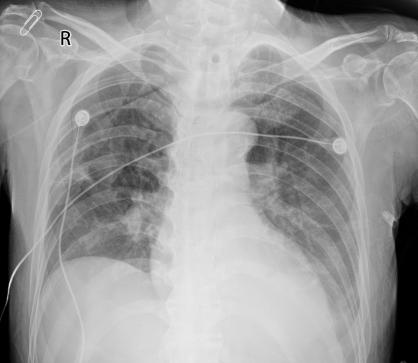

▌影像学检查:

2023-08-30胸部CT显示:(1)双肺炎性变,双侧胸腔积液。(2)心脏增大,心包积液,主动脉、冠脉钙化斑。

△外院胸部CT(2023-08-30)

2023-09-08胸部CT示双肺炎症较前减少,双侧胸腔积液较前减少,右肺部分不张,心包积液,主动脉、冠脉钙化斑。

△外院胸部CT(2023-09-08)

9月18日,胸片示双肺炎症表现,对比院前CT进展。痰培养结果显示:CRAB,菌落计数(++++)。此外,患者体温有升高趋势,考虑CRAB可能为致病菌。根据2023年美国感染病学会(IDSA)抗微生物药物耐药革兰阴性菌感染治疗指南建议[1],结合药敏结果,并考虑患者经济负担等因素,给予患者头孢哌酮/舒巴坦(3 g,ivdrip,q6h,维持3h)+米诺环素(200 mg,po,q12h)抗感染治疗。

△胸片(2023-09-18)